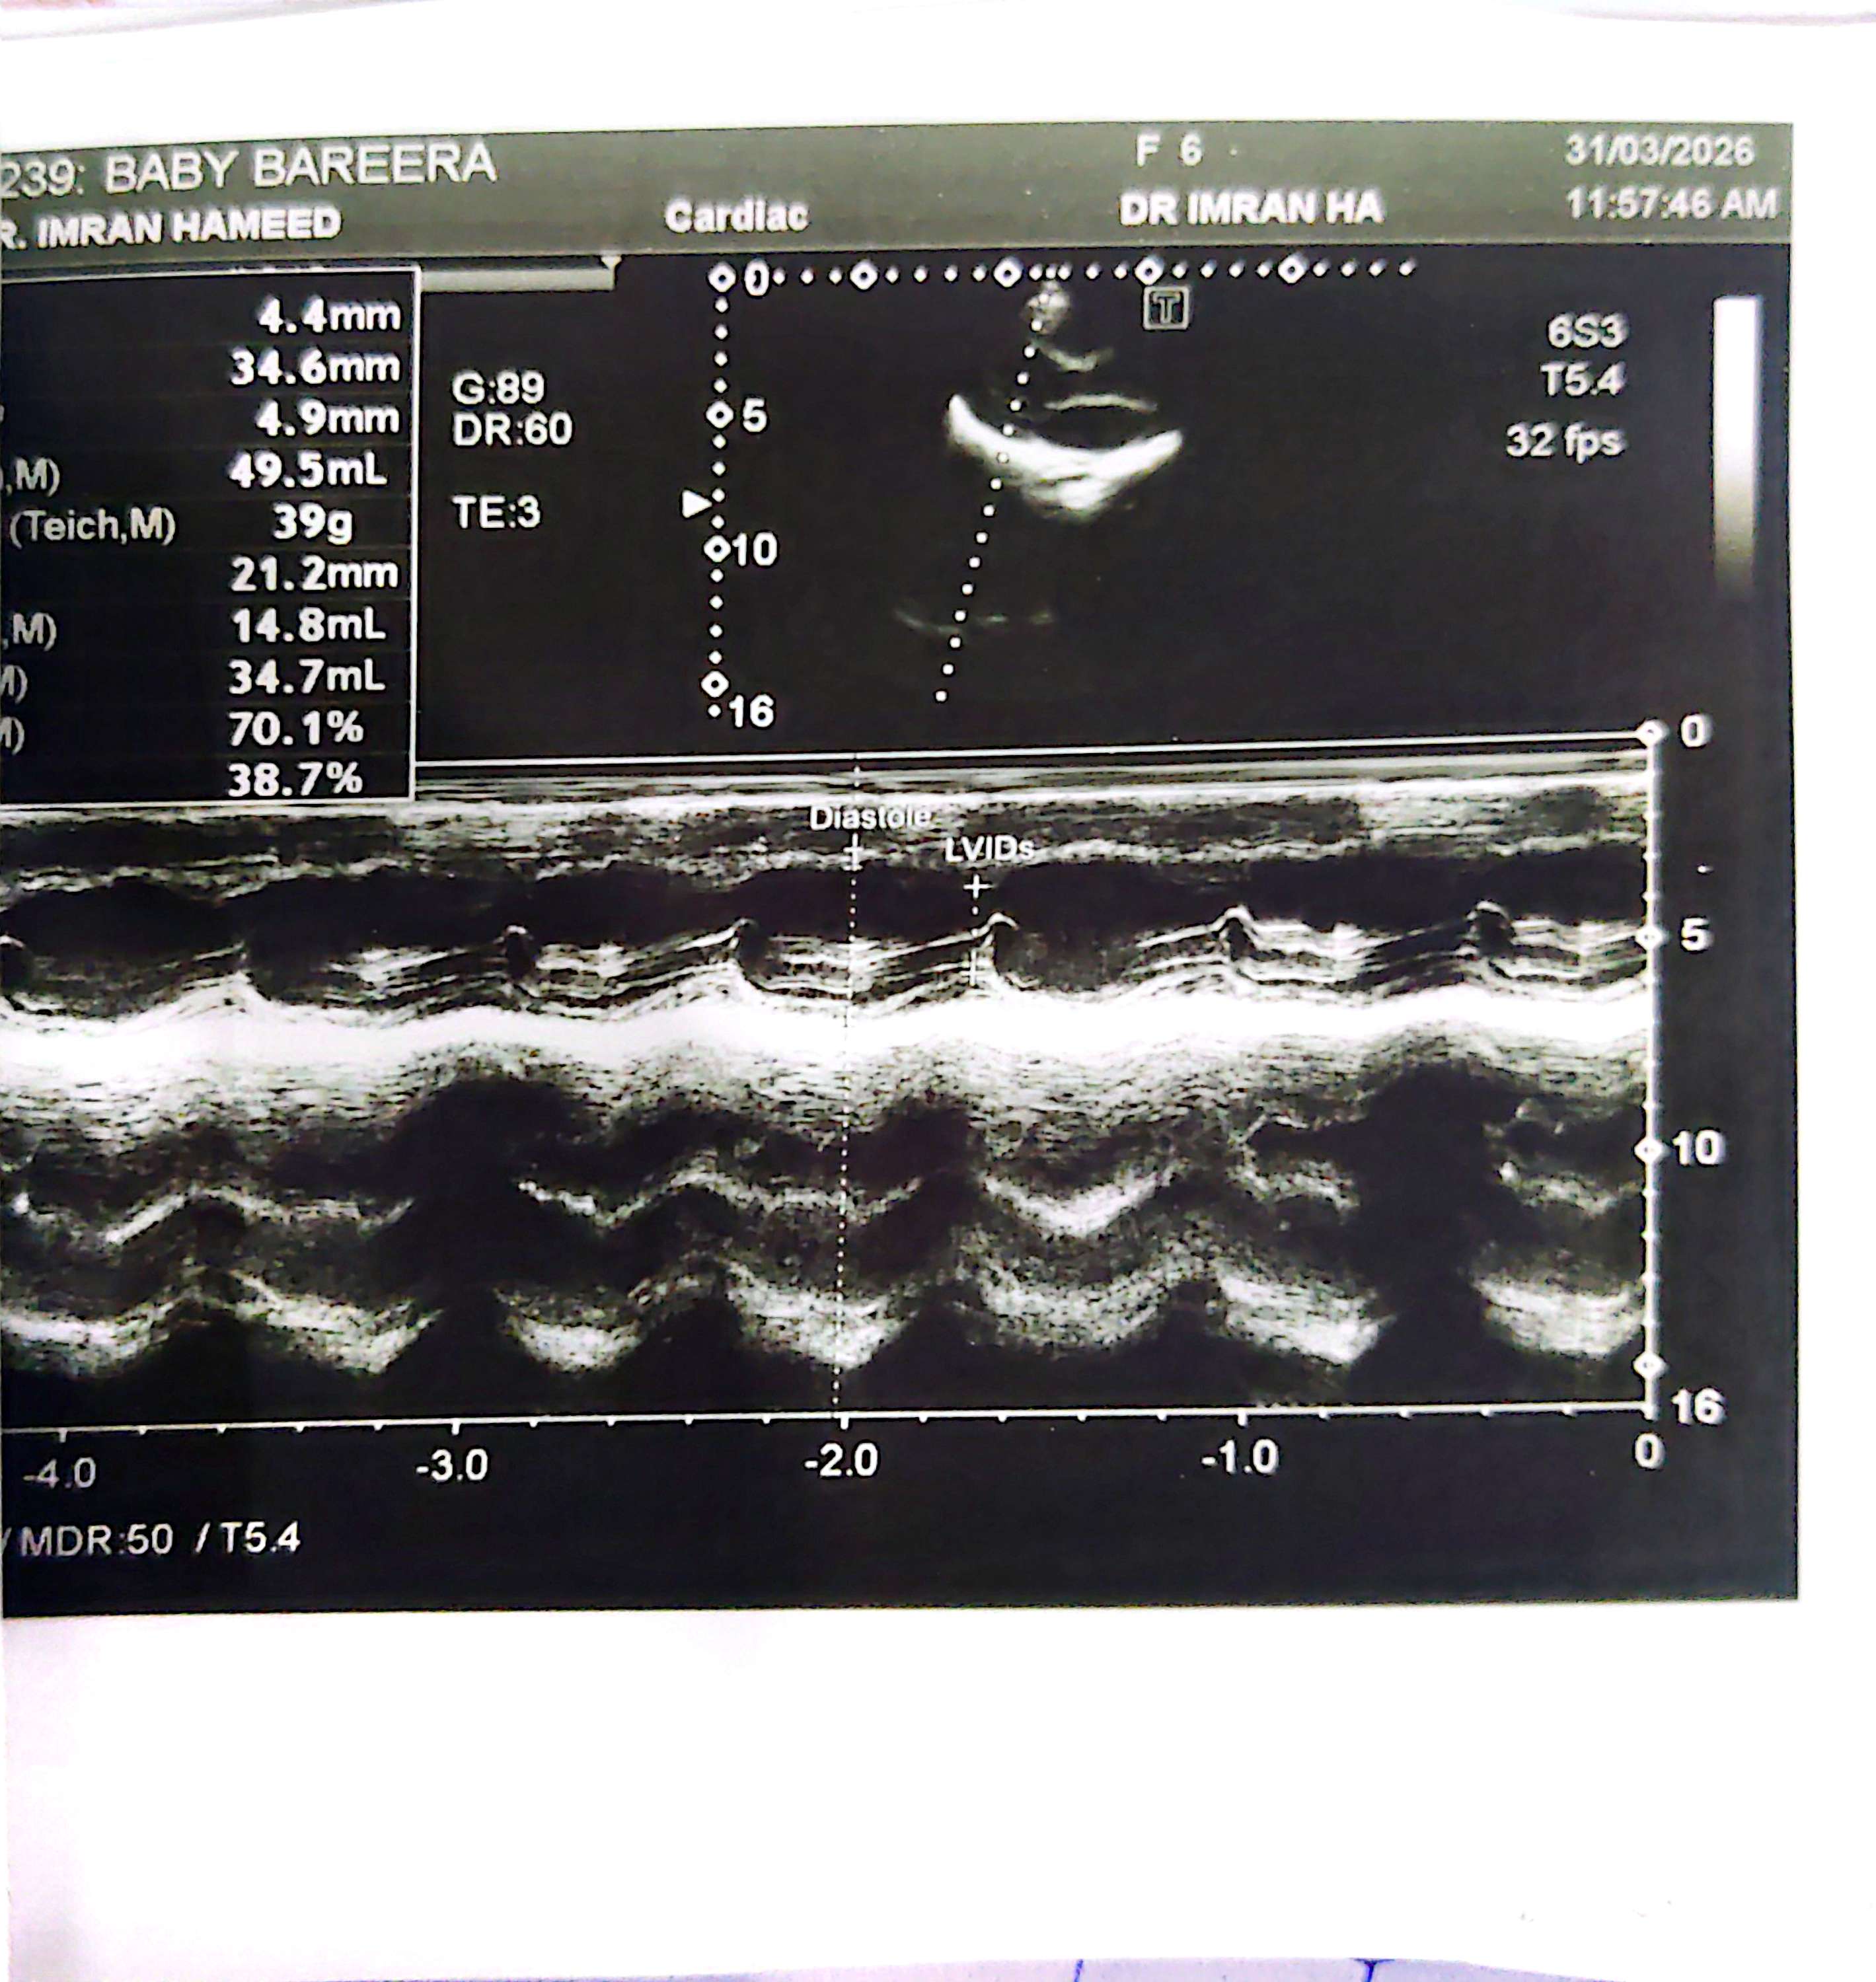

Assalamualaikum my daughter is 6 years old now, at the time of birth as per Dr her heart beat was a bit disturb they suggested us to see a cardiologist we came to you when she got 6 month old in NICVD for follow up got her echo and you cleared her but now we went to a doctor for her normal checkup he told us to get her echo done and refer to you again.Iam attaching her reports here.

Epstein anamoly , with ASD and tricuspid regurgitation and pulmonary hypertension. Four problems. The ASD can be closed . The pulmonary hypertension can medically mitigated.